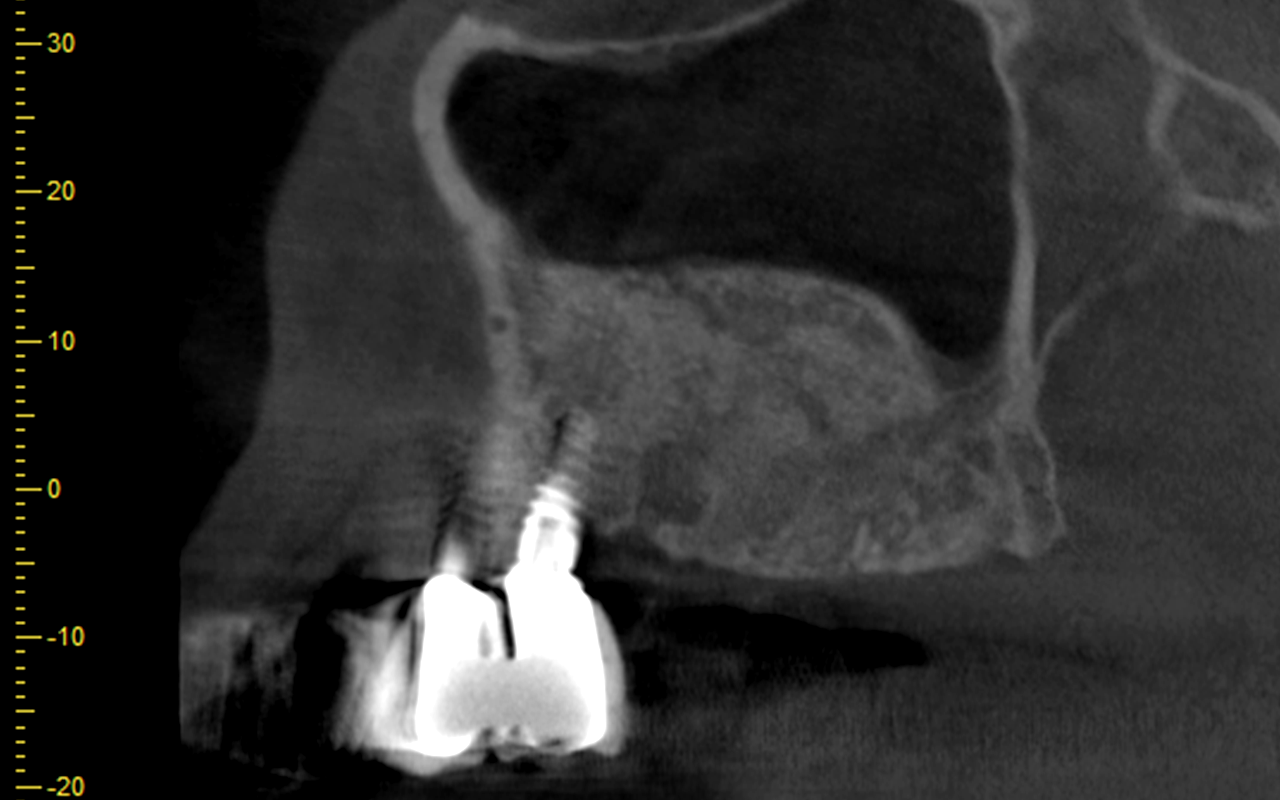

Patient treatment by faculty will focus on advanced surgical treatment with implant placement and GBR/soft tissue grafting in the anterior esthetic zone.

Full arch patient surgery with 3D surgical and stackable guides, implant scanning protocols with 3Shape and photogrammetry with PIC scanner and delivery of 3D printed full-arch provisionals.